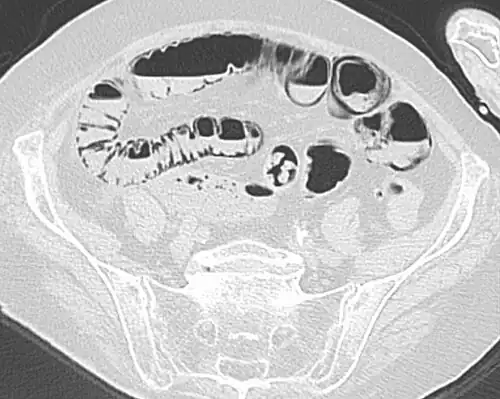

Pneumatosis intestinalis at computed tomography in intestinal ischemia. Lung window for better representation of the gas deposits in the intestinal walls. Coronal reconstruction. -

Pneumatosis intestinalis in the coronal computed tomography in lung window. It can be seen next to gas entrapment in the bowel wall and gas in the stomach wall and in numerous vessels, including the portal vein into the liver. -

Pneumatosis intestinalis in computed tomography with intestinal ischemia. Lung window for better representation of the gas deposits in the intestinal walls. -